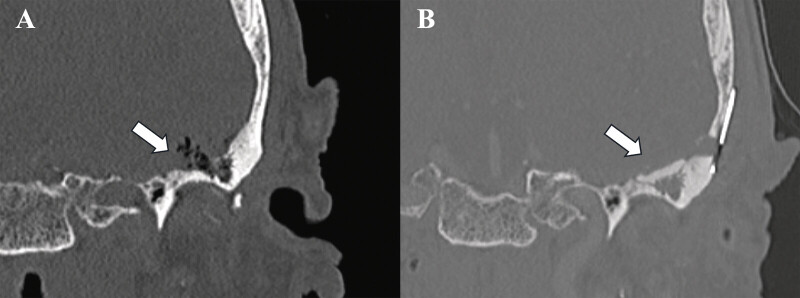

Case presentations: Three patients presenting with otalgia and TMJ tenderness were found to have intracranial cysts communicating with the TMJ. Two patients had been transferred with suspected intracranial abscesses; one presented for workup of headache and trigeminal neuralgia. All three demonstrated elevation of inflammatory markers. Two patients had TMJ aspiration, notable for leukocytosis and crystalline deposition, another had frank purulence. One patient demonstrated pneumocephalus within the cyst on imaging. The intracranial cysts ranged from 1.2 to 3.3 cm in maximum diameter, with their bony defects ranging from <1 to 4 mm. Two patients underwent craniotomy, cyst resection, and repair of the middle fossa defect, while the third opted for observation. Pathology of the white gelatinous fluid within the two resected growths demonstrated benign cysts.